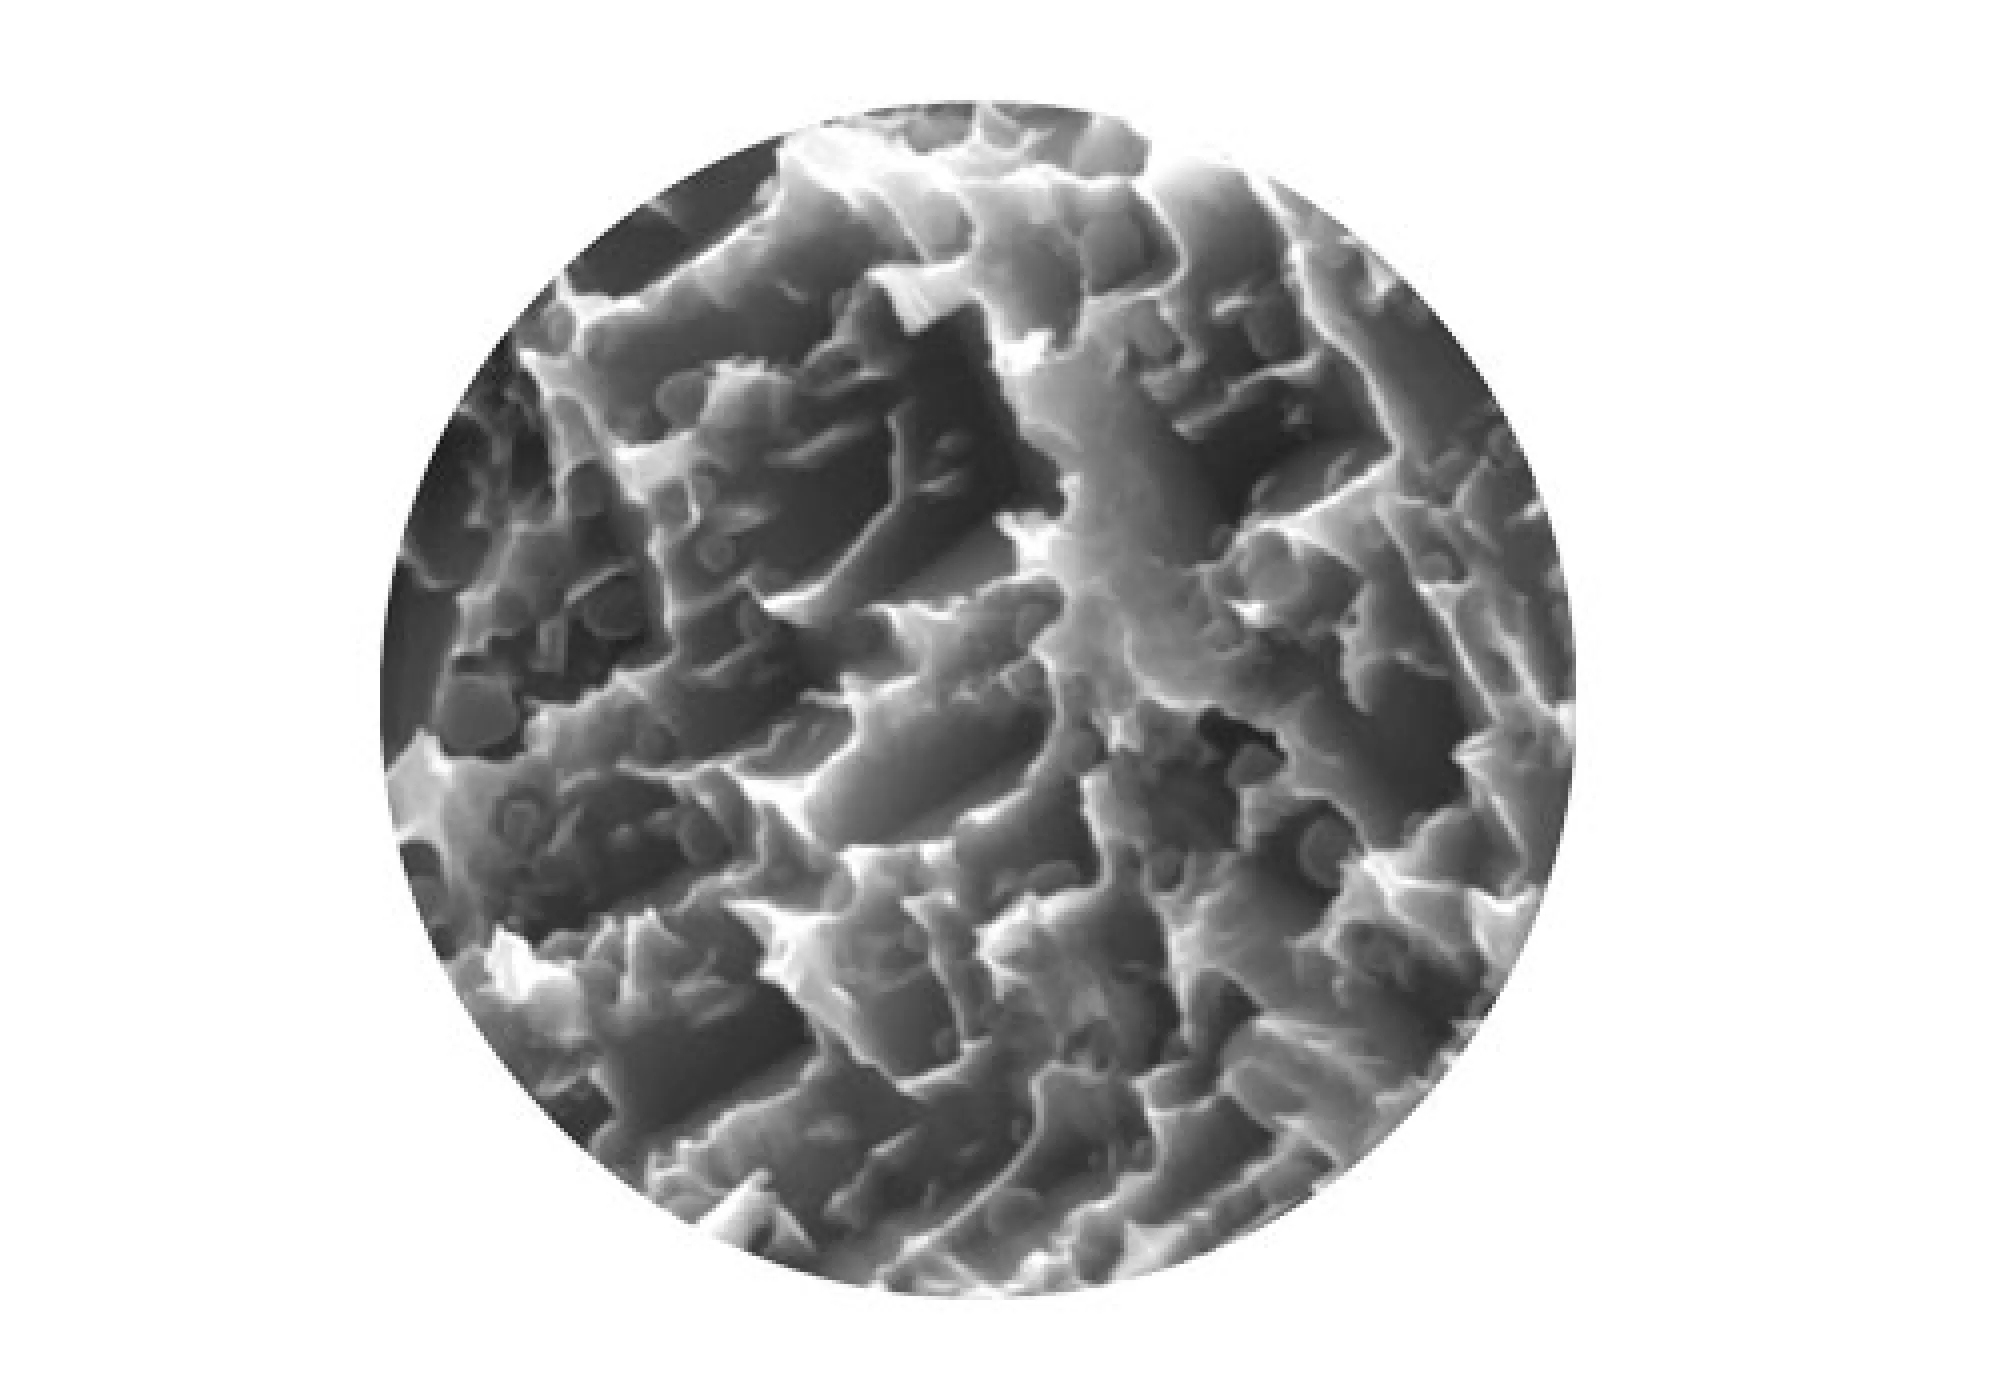

ネオスインプラントはイギリスに本社を持つネオス社というインプラントメーカーが、スウェーデンのイエテボリ郊外で開発、製造しているインプラントです。 このインプラントは、2000年にネオス社が創立されて以来販売され始めた新しいインプラントにも関わらず、たちまちインプラント先進国の間で一 流インプラントとして位置づけられました。 インプラントメーカーにはいくつか名だたる一流メーカーが存在しますが、そのような歴史の長いメーカーともはや同レベルに評価されているネオスインプラントには、いくつか突出した素晴らしい点があります。 また、このインプラントは企業主導ではなく、イエテボリ大学という教育機関で研究されていることも、多くの歯科医師から大きな信頼を得ている理由となっています。当院では、「自分が処置されてもよいと思えるインプラントを使いたい」という思いから、このネオスインプラントを取り入れています。 ネオスインプラントは、インプラント体表面が水になじみやすいよう、「エレクトロウェッティング」という技術を採用しています。 そのため、インプラントを埋め込んだ後、表面上で血液や、その成分の浸透によるタンパク質や生体分子がインプラント表面によく密着し、インプラントのねじの深部まで骨の形成が促進され、しっかりと初期に固定されます。 インプラント表面に施されている粗面化処理(表面を粗くする処理)によっても、骨と接触する表面積が増し、より強力な結合が得られるようになっています。 この処理はインプラントの歯根部分にはより粗めに、歯茎に近い部分にはよりマイルドに仕上げることにより、インプラント周囲炎を起こしにくいようなエ夫がなされています。 インプラントの素材はチタン製がほとんどですが、純チタンのもの、純チタンでないものなど様々なものが存在します。ネオスインプラントは、特別な製造 法により、チタンの純度を変えることなく、商業用純チタングレードIVを超える強度の強化チタンとなっています。 これにより、インプラントの破折のリスクを大幅に減らすことができます。また、純チタンであることにより、金属アレルギーのリスクも大幅に減らすことができ、金属アレルギーが心配な方にもより安心してお使いいただけます。 ネオスインプラントは、通常だと初期固定が得られないような、骨の質があまり良くない部分にでも対応できるという強みがあります。つまりどんなに骨の状態がやわらかすぎても、硬くすぎても対応できるようになっています。 その秘密として、まず、優れたドリルシステムが挙げられます。ネオスインプラントのドリルシステムは、インプラントを埋める穴を正確な位置に開けるのが容易なシステムになっています。 また、ネオスインプラント独自のTCFという二重構造のネジの形状のデザインにより、あらゆる骨質において、確実に安定が得られるようになっています。ネジはインプラントの先端にまで及んでおり、骨内での安定性をさらに高めて くれます。 LMGでは実際に当院で行ったインプラント手術の症例を公開しております。歯を失ってしまった方や、歯周病等で歯を残すことが困難と診断された方は当院でのインプラント治療なら綺麗で咬みやすい口腔内を取り戻すことができるかもしれません。ぜひチェックしてみてください。ネオス(NEOSS)インプラント

骨とインプラントの初期固定がしっかりと得られる

インプラント周囲炎を起こしにくい素材